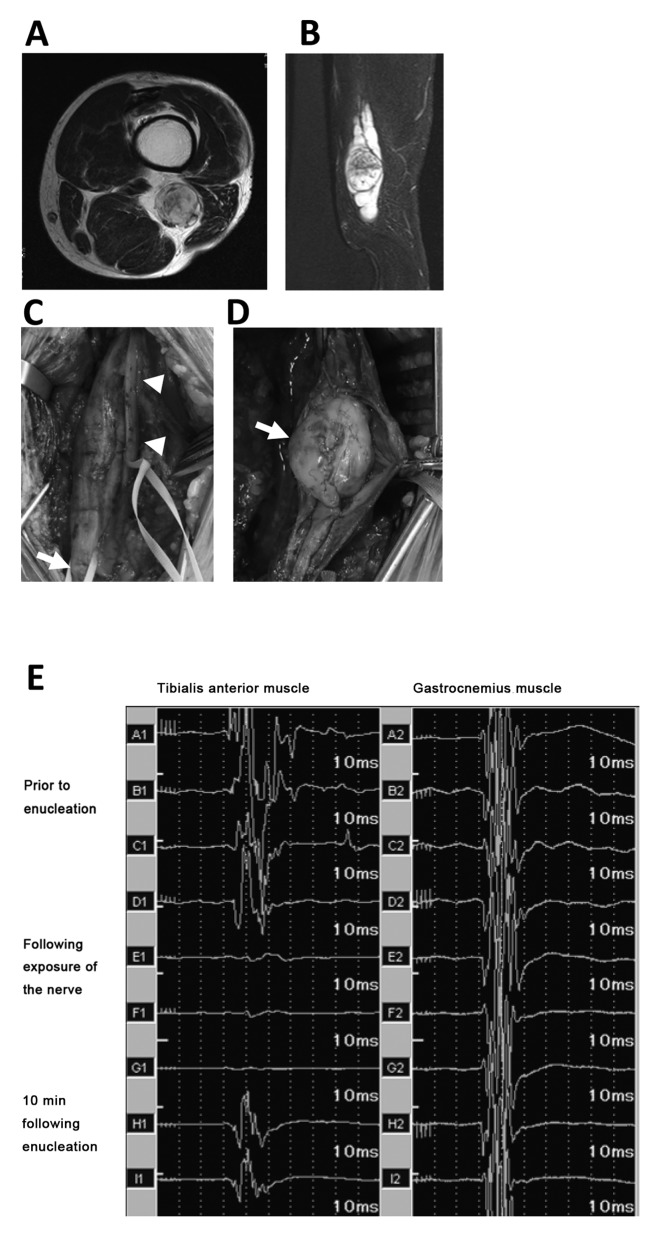

Figure 2.

A case of schwannoma affecting the sciatic nerve (case no. 21). (A) Axial and (B) sagittal views of T2-weighted magnetic resonance imaging of the affected area. (C) The tibial (arrowheads) and common peroneal (arrow) nerves were exposed prior to enucleation. (D) The capsule was cut and enucleation performed with the tibial and common peroneal nerves intact. (E) MEP readings of the tibialis anterior muscle (left column) and gastrocnemius muscle (right column) remained intact prior to enucleation (top four waves). Following tumor enucleation, the MEP was completely lost (E1 and F1) but recovered after 10 min (H1). The patient in this case developed complete peroneal nerve palsy postoperatively. MEP, motor-evoked potential.

In 3/23 cases, MEP decreased to <50% of the preoperative value (Table I). In cases no. 4 and 12, the schwannoma occurred in the calf and involved the common peroneal nerve and tibial nerve, respectively. There was no postoperative neurological deficit in either case; however, because a tourniquet was used during surgery, these results were thought to be false positives. In another case where MEP decreased by <50% (case no. 21), the tumor originated from the sciatic nerve (Fig. 2A and B). During surgical exposure of the tumor, and the tibial and peroneal nerves, the MEP remained intact (Fig. 2E). Following enucleation of the tumor from the capsule, with preservation of the affected nerve, the potential was completely lost (Fig. 2E). After 10 min, the MEP recovered to 61% of the preoperative MEP. The patient in this case presented with common peroneal palsy postoperatively (Table I). In another case in which there was postoperative motor loss (case no. 15), the schwannoma involved the lumbar nerve root; however, the MEP did not change intraoperatively (data not shown). The patient had loss of muscle strength around the hip and knee that recovered 3 months following surgery. A total of 3 other patients (case no. 2, 9 and 10) had sensory disturbance in the area of the involved nerve (ulnar or peroneal) postoperatively (Table I). The sensory disturbance was transient in all 3 cases and gradually resolved with 1–4 months. Preoperative neurological symptoms were present in 2 cases (case no. 2 and 6). There were no postoperative complications in either case. One patient (no. 2) had sensory disturbance postoperatively described above, and the other (no. 6) had no postoperative complications.